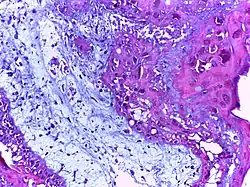

![]() | Foreign body granuloma | Granulomatous reaction to keratin characterized by foreign body giant cells and chronic inflammatory cells. | Category: Histopathology of foreign body granuloma | Foreign body granuloma, silicone granuloma |